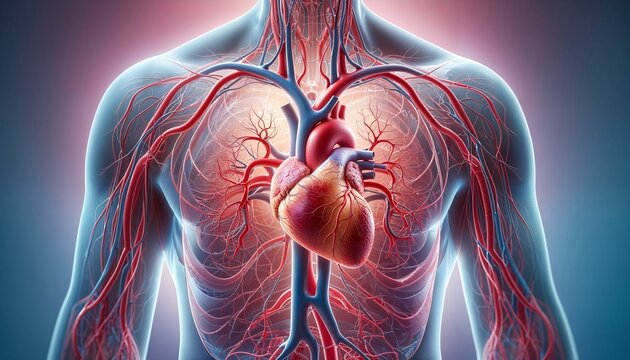

2. أمراض القلب والأوعية الدموية

أحد أسباب الوفاة الرئيسة حول العالم، وتشمل ارتفاع ضغط الدم وأمراض الشريان التاجي والسكتات الدماغية، ولكن لا تخف فالعلاقة بين الوقاية من الأمراض القلبية والرياضة وطيدة؛ إذ يُعد النشاط البدني أقوى الأسلحة لمكافحة هذه الأمراض. في ما يلي، نوضح كيف:

- تقوية عضلة القلب كأية عضلة أخرى في الجسم تقوى بالتمارين الصحيحة وممارسة الرياضة بانتظام؛ إذ يضخ القلب الدم بكفاءة أعلى، فيقل الجهد المبذول، وتتحسن الدورة الدموية، وينخفض ضغط الدم المرتفع أيضاً.

- تحسين مستويات الكوليسترول الجيد(HDL) وتقليل مستويات الكوليسترول الضار(LDL)، والدهون الثلاثية أيضاً، فيقل خطر تراكم الترسبات في الشرايين.